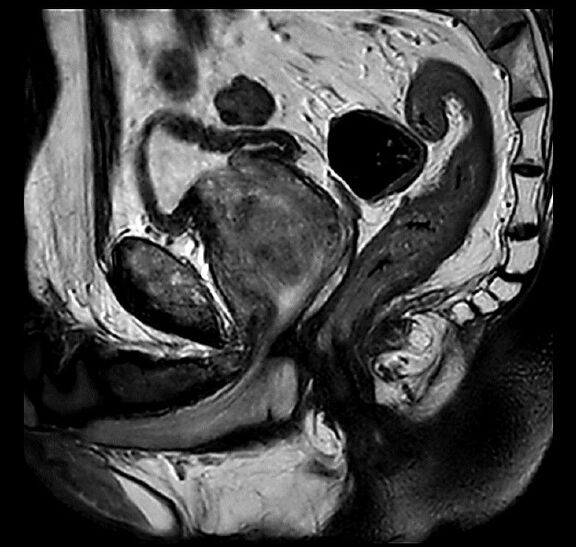

Beispiele von MRT-Prostata Aufnahmen

Die MRT wird meist zur Abklärung von Auffälligkeiten in der Prostata eingesetzt, die bei anderen Untersuchungen wie einer Tastuntersuchung, einer Blutuntersuchung oder einem PSA-Test festgestellt wurden. Dazu gehören zum Beispiel eine Vergrößerung der Prostata oder der Verdacht auf Prostatakrebs. Neben der Diagnose von Prostatakrebs können auch andere Erkrankungen wie Entzündungen oder gutartige Vergrößerungen der Prostata im MRT erkannt werden. Dies ermöglicht eine gezielte und schnelle Therapie.

Ein großer Vorteil der MRT im Vergleich zu anderen Verfahren ist die hohe Genauigkeit bei der Erkennung von Prostatakrebs im Vergleich zu anderen Verfahren. Die MRT kann die Gewebestrukturen der Prostata gezielt abbilden und so kleinste Veränderungen sichtbar machen. Zudem ist die Untersuchung schonender und kommt ohne den Einsatz von Röntgenstrahlung aus.